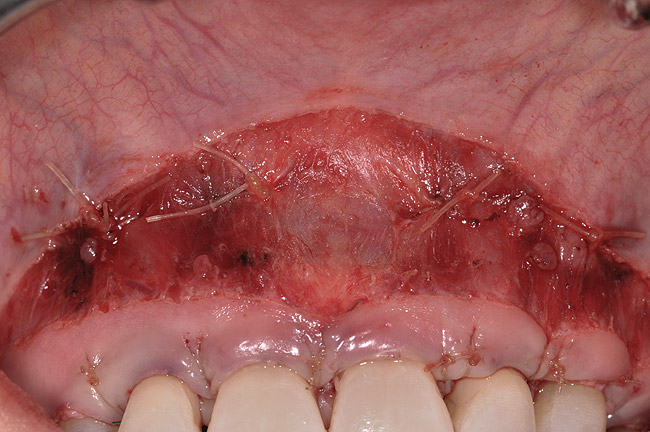

After administration of an appropriate local anesthetic, a laser-assisted split-thickness vestibuloplasty was performed superior to the mucogingival junction from the right central incisor to the left first premolar region (Figure 7). Prior to any incisions being performed, a 20-mm x 40-mm dermal matrix graft (Puros Dermis), a 0.8-mm to 1.7-mm thick piece of tissue, was trimmed to appropriate length and width to correct the gingival defect present (Figure 8). The tissue graft was sized to 6 mm in height and spanned to the mesial line angle of the left central incisor to the distal line angle of the left canine area. The dermal matrix graft was rehydrated with the patient’s own platelet-rich plasma solution, which was harvested from 20 cc of whole blood collected immediately prior to the surgical procedure (Figure 9).

Fig 8. Dermis selected, and sized for defect.

Figure 8

Fig 9. Acellular dermal matrix reconstituted with nonactivated platelet-rich plasma.

Figure 9